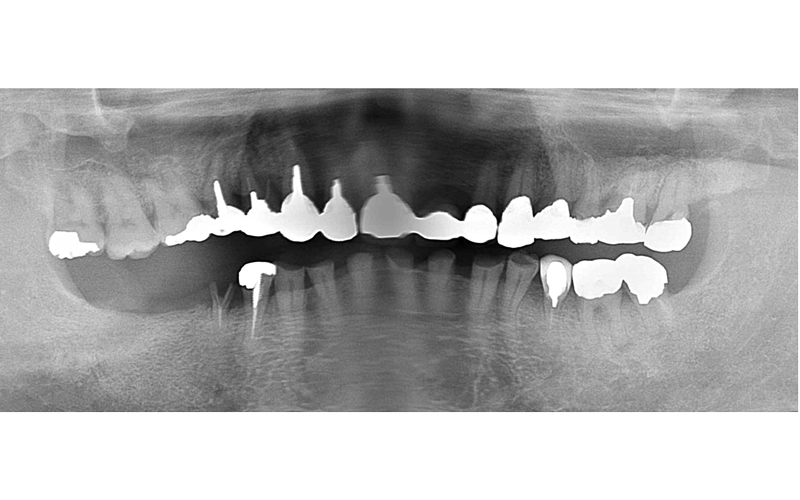

Before

初診時